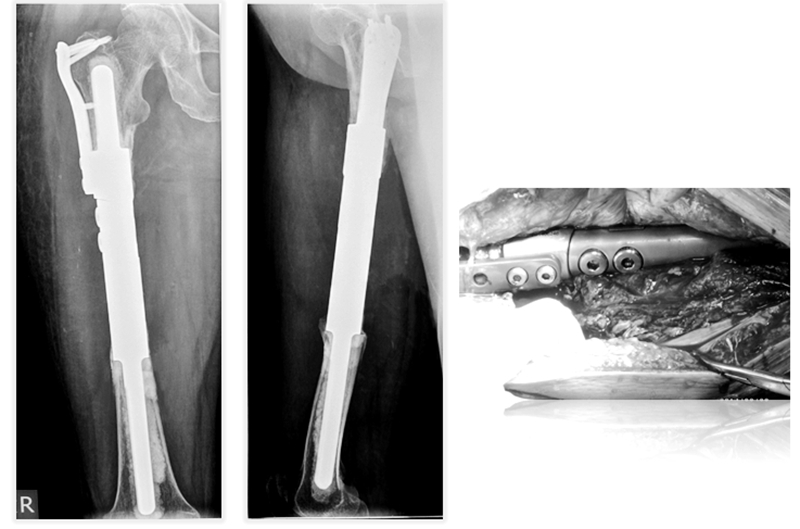

患者女性,68岁,乳腺癌病史,右股骨中段病理性骨折,股骨长段溶骨性破坏,并有跳跃病灶。病变的长度为16cm,病灶近端在小转移水平,因为近端髓腔柄较短,故选择A区骨干假体。经病理诊断为转移性腺癌,术后2周患者拆线后即可离床活动。

术后资料